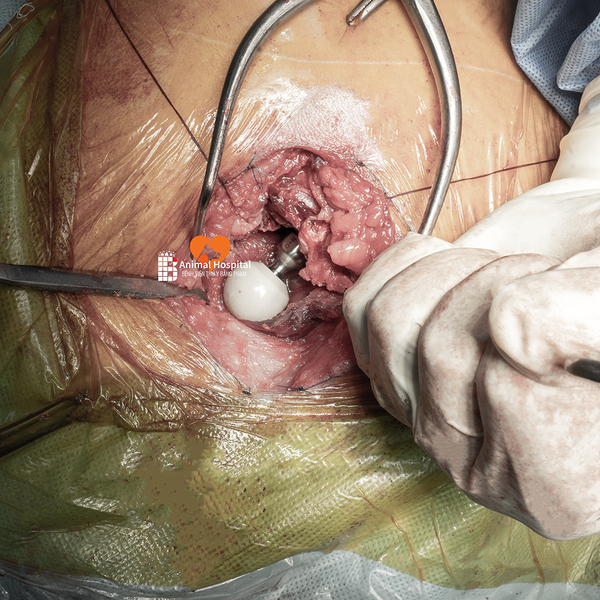

🔧 Giải pháp phẫu thuật | Total Hip Replacement (THR)

Sau khi đánh giá tổng thể tình trạng thoái hóa khớp háng ở chó, team bác sĩ tại Bệnh Viện Thú Y Bằng Phạm đã quyết định thực hiện thay khớp háng toàn phần bằng hệ thống tiên tiến 𝐁𝐥𝐮𝐞𝐒𝐀𝐎 𝐁𝐢𝐨𝐧𝐢𝐜 𝐇𝐢𝐩 – một trong những công nghệ hàng đầu hiện nay trong lĩnh vực cấy ghép khớp ở thú y.

⚙️ Cấu hình sử dụng | Implant Configuration

- Chỏm đùi: PEEK 20mm

- Cup acetabulum: Titan không xi măng 25mm

📸 Kết quả sau phẫu thuật thái hóa khớp háng ở chó | Post-op Results

Ảnh X-quang hậu phẫu cho thấy:

- Implant được đặt đúng vị trí

- Trục khớp chuẩn xác

- Tiếp xúc xương tốt – là tiền đề lý tưởng cho sự phục hồi.